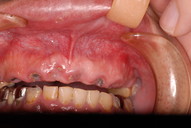

歯無しにならない長い話し

今回約1年近くかかった方のとりあえずの治療が終了しました。

でも、歯医者がどんなに何かを被せても元の健康な状態になった訳ではないのです。歯医者さんは、何かを詰めたり被せたりしますけれど、これは、修復でありお口の中に何か造作をしたに過ぎません。

磨かなければ、磨けなければすべて崩壊して入れ歯、或いは人工歯根へまっしぐらなんです。

お口の中の病気は基本的には、虫歯、歯周病、そして神経の処置以外にはあまりないのです。ですからばい菌で悪くなる訳ですからばい菌を毎日毎日取り除く以外に崩れていくのを止める方法はないのです。

ブラシの使い方に習熟しましょう。

最初の状態です。若いのにすぐ外れる入れ歯をいれていらっしゃいました。

DSC_0167DSC_0162

DSC_0166DSC_0165

DSC_0164

そしてひとまず終了した状態です。

DSC_0018DSC_0023

DSC_0027

このように綺麗になりましたが元の健康な状態になったのではないのです。ばい菌が歯の周りから採れていなければ元の木阿弥。

おそらく差し歯にもできず入れ歯かインプラントという人工歯根になる事でしょう。いやはやいくら費用がかかるのやら患者さんのことながらため息が出ます。

歯医者では病気を治していないことが多いのです。ただ詰めたり被せたりしているのに過ぎません。注意しないともっとひどいことになります。

そして、虫歯や歯周病、そして神経の処置は医療行為ですから誰でも100%うまくいくかというと、うまくいっていないことが多いのです。医療行為は難しいのです。良い歯の医者に当たる事を祈ります。

歯に何かを被せることは医者のやることではなくお口の大工さんがやることなのです。ですから歯医者は、大工と医者を同時にやっていることになりますね。

歯医者から口腔科の医師へ脱皮しなければなりません。日々精進あるのみ!